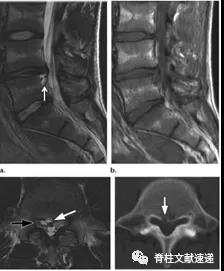

图注:椎间盘囊肿

图注:23岁男性,椎间盘囊肿。术中见波动的椎间盘囊肿并切除。